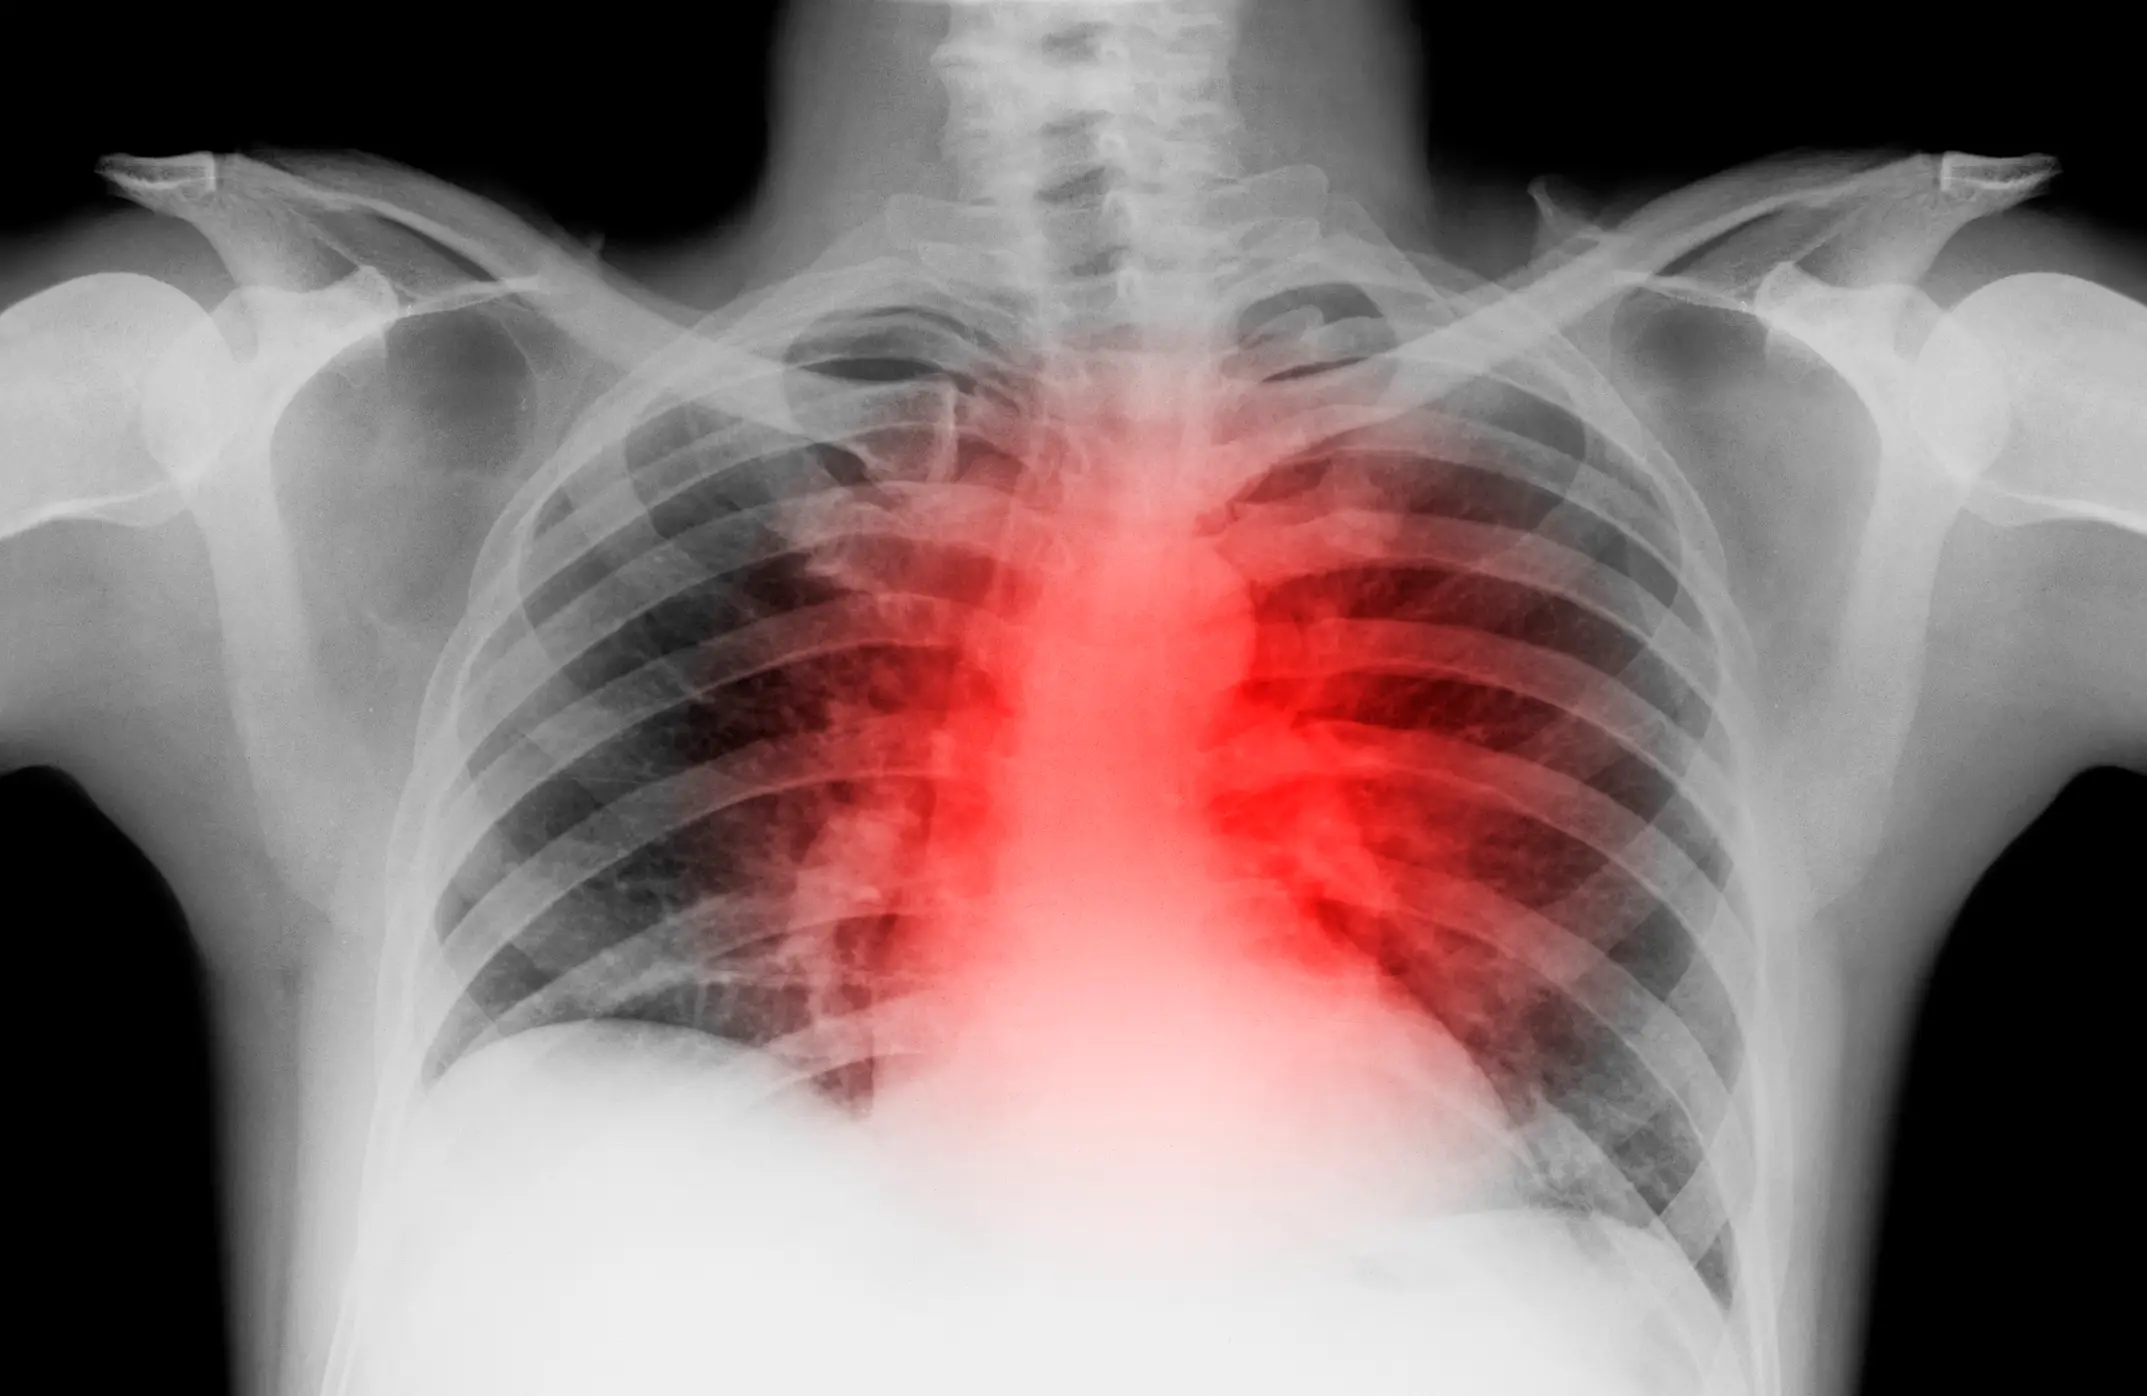

Dr Yaranov went on to explain that he's seen patients who've spent years on such diets suffer from high cholesterol, endothelial (a thin layer of cells lining the blood vessels) dysfunction, chronic inflammation and a premature buildup of fats and cholesterol in the arteries.

He said that while a person's exterior body may appear to be fit and healthy, the inside can often tell a different story, adding: "I’ve cared for 'fit' 35-year-olds with heart attacks.

"No symptoms. No warning. Just a ticking time bomb."